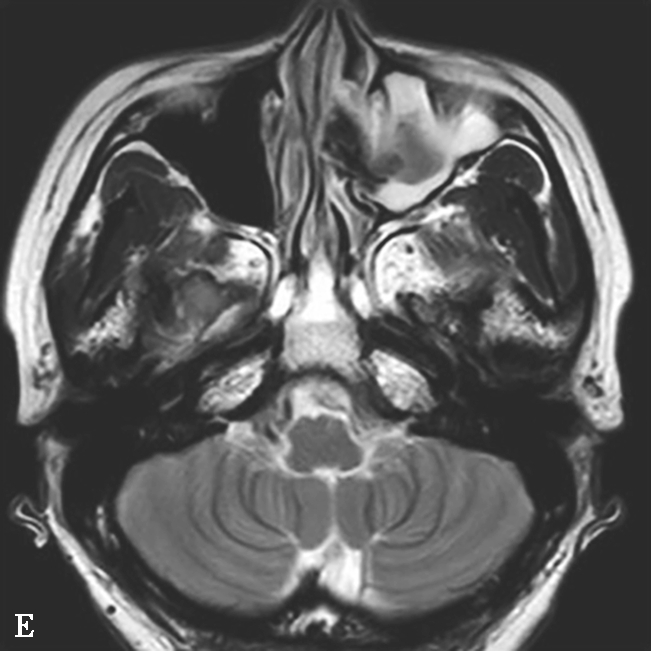

图1-3-24 嗜酸细胞增多黏液性鼻窦炎

A、B.横断面及冠状面CT骨窗,示双侧额窦、筛窦、上颌窦及蝶窦腔充填软组织影,密度不均匀,见多发斑片状磨玻璃样密度影“双重密度影”;双侧中、总鼻道见软组织影充填;C~E.横断面T 1 WI、T 2 WI及冠状面T 1 WI,示全组鼻窦窦腔充填长T 1 、混杂短到长T 2 信号影,双侧中鼻道、总鼻道及上颌窦窦口区可见小斑片状略短T 1 混杂等到短T 2 信号影